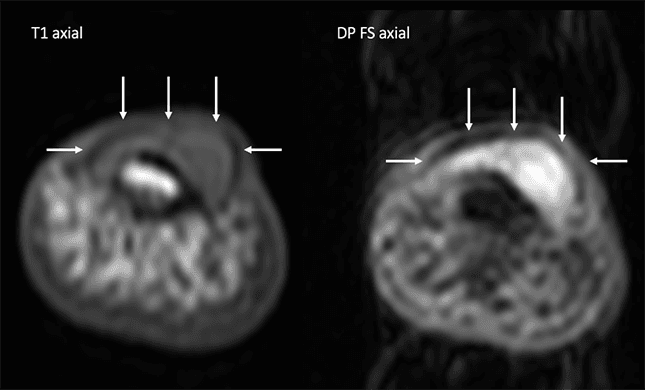

RM do primeiro quirodáctilo em plano axial, sequências ponderadas em T1 e em densidade protônica com saturação de gordura.

A lesão nodular determina discreto remodelamento da cortical óssea subjacente e mede cerca de 0,7 cm x 0,5 cm.